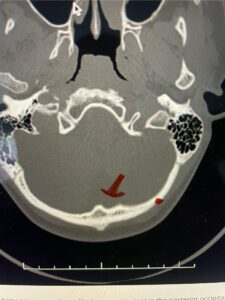

Fig. 4b: Axial T2-weighted cervical MRI demonstrating severe spinal cord compression from atlanto-axial instability (red arrow)

Cervical x-rays revealed a significantly increased atlanto-axial interval (Fig. 5) On review of her imaging studies it was noted that the right C2 isthmus was very thinned by the vertebral foramen (Figs 6a, b, and c) which would make an attempt at placing a C2 pars screw dangerous. A decision was made to perform an occipital-cervical fusion because only possible unilateral fixation and an extensive C1 laminectomy to be performed eliminating a fixation point if a more traditional C1-C2 was performed. Even if C1 lateral mass screws were able to be placed one could only perform a unilateral screw construct fixation to C2. We performed an occipital cervical fusion down to C4 to get enough inferior fixation and C1 laminectomy. The decompression went well. We placed a left unilateral pars screw and bilateral C3 and C4 lateral mass screws. We placed three 12 mm screws in the midline keel (Fig. 7). Postoperatively the patient had all around improvement in her symptoms and did not qualify for rehab. Her post op films at 6 weeks (Fig. 8)